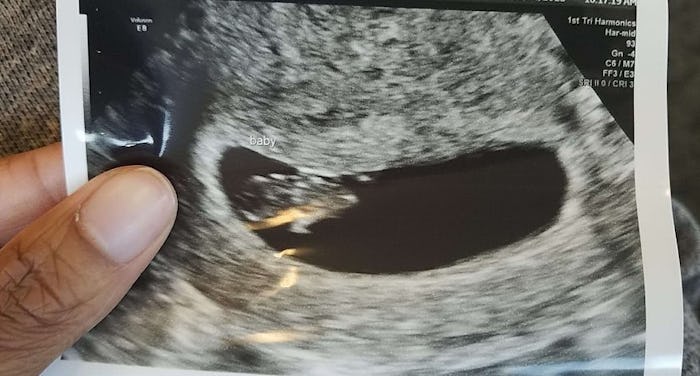

This month felt so surreal. I went through the highs and lows of knowing there was a new baby joining our family, and my brain is still swirling. I had about one week to be excited before the pain came in. If that sounds like a very short time, it is.

Seeing that positive test set me into shock. After so many months of negatives, I thought I was dreaming. Truthfully, I’d just gotten to the point where mentally I was ready to give up to protect myself. But I didn’t have time to process it because I had a trip to Washington, around the same time the pregnancy discomfort kicked in.